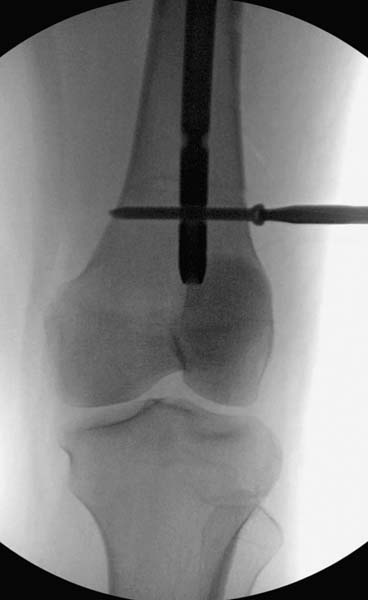

Вообщем.., больная поступает около 2.00 дня и дальнейщая хронология: 2.27 PМ рентген грудной клетки; 2.54 РМ рентген бедра; 2.53-3.06 КТ скан, всего около 2000 срезов. Из-за беспокойства пациента (алкоголь), множественные переломы ребер – трубка в превральную полость и интубация. Около 3.45 в операционной эксплуараторная лапароскопия с последующим ушиванием брюшной полости.

Больная стабильная после хирургических мероприятии и получив добро, приступили к закрытому вправлению таранной кости с укладкой наружного фиксатора. Затем укладка больную на бок и открытый остеосинтез перелома-вывиха головки бедра.

Остеосинтез бедра не стали делать из-за множественных переломов ребер с ушибом грудной клетки и поэтом у закончили фиксацию бедра наружным фиксатором.

Около 11.00 вечера больная переведена в реанимацию, без сознания, но стабильная.. На третьий день провели стабилизацию перелома бедра антеградным остеосинтезом.